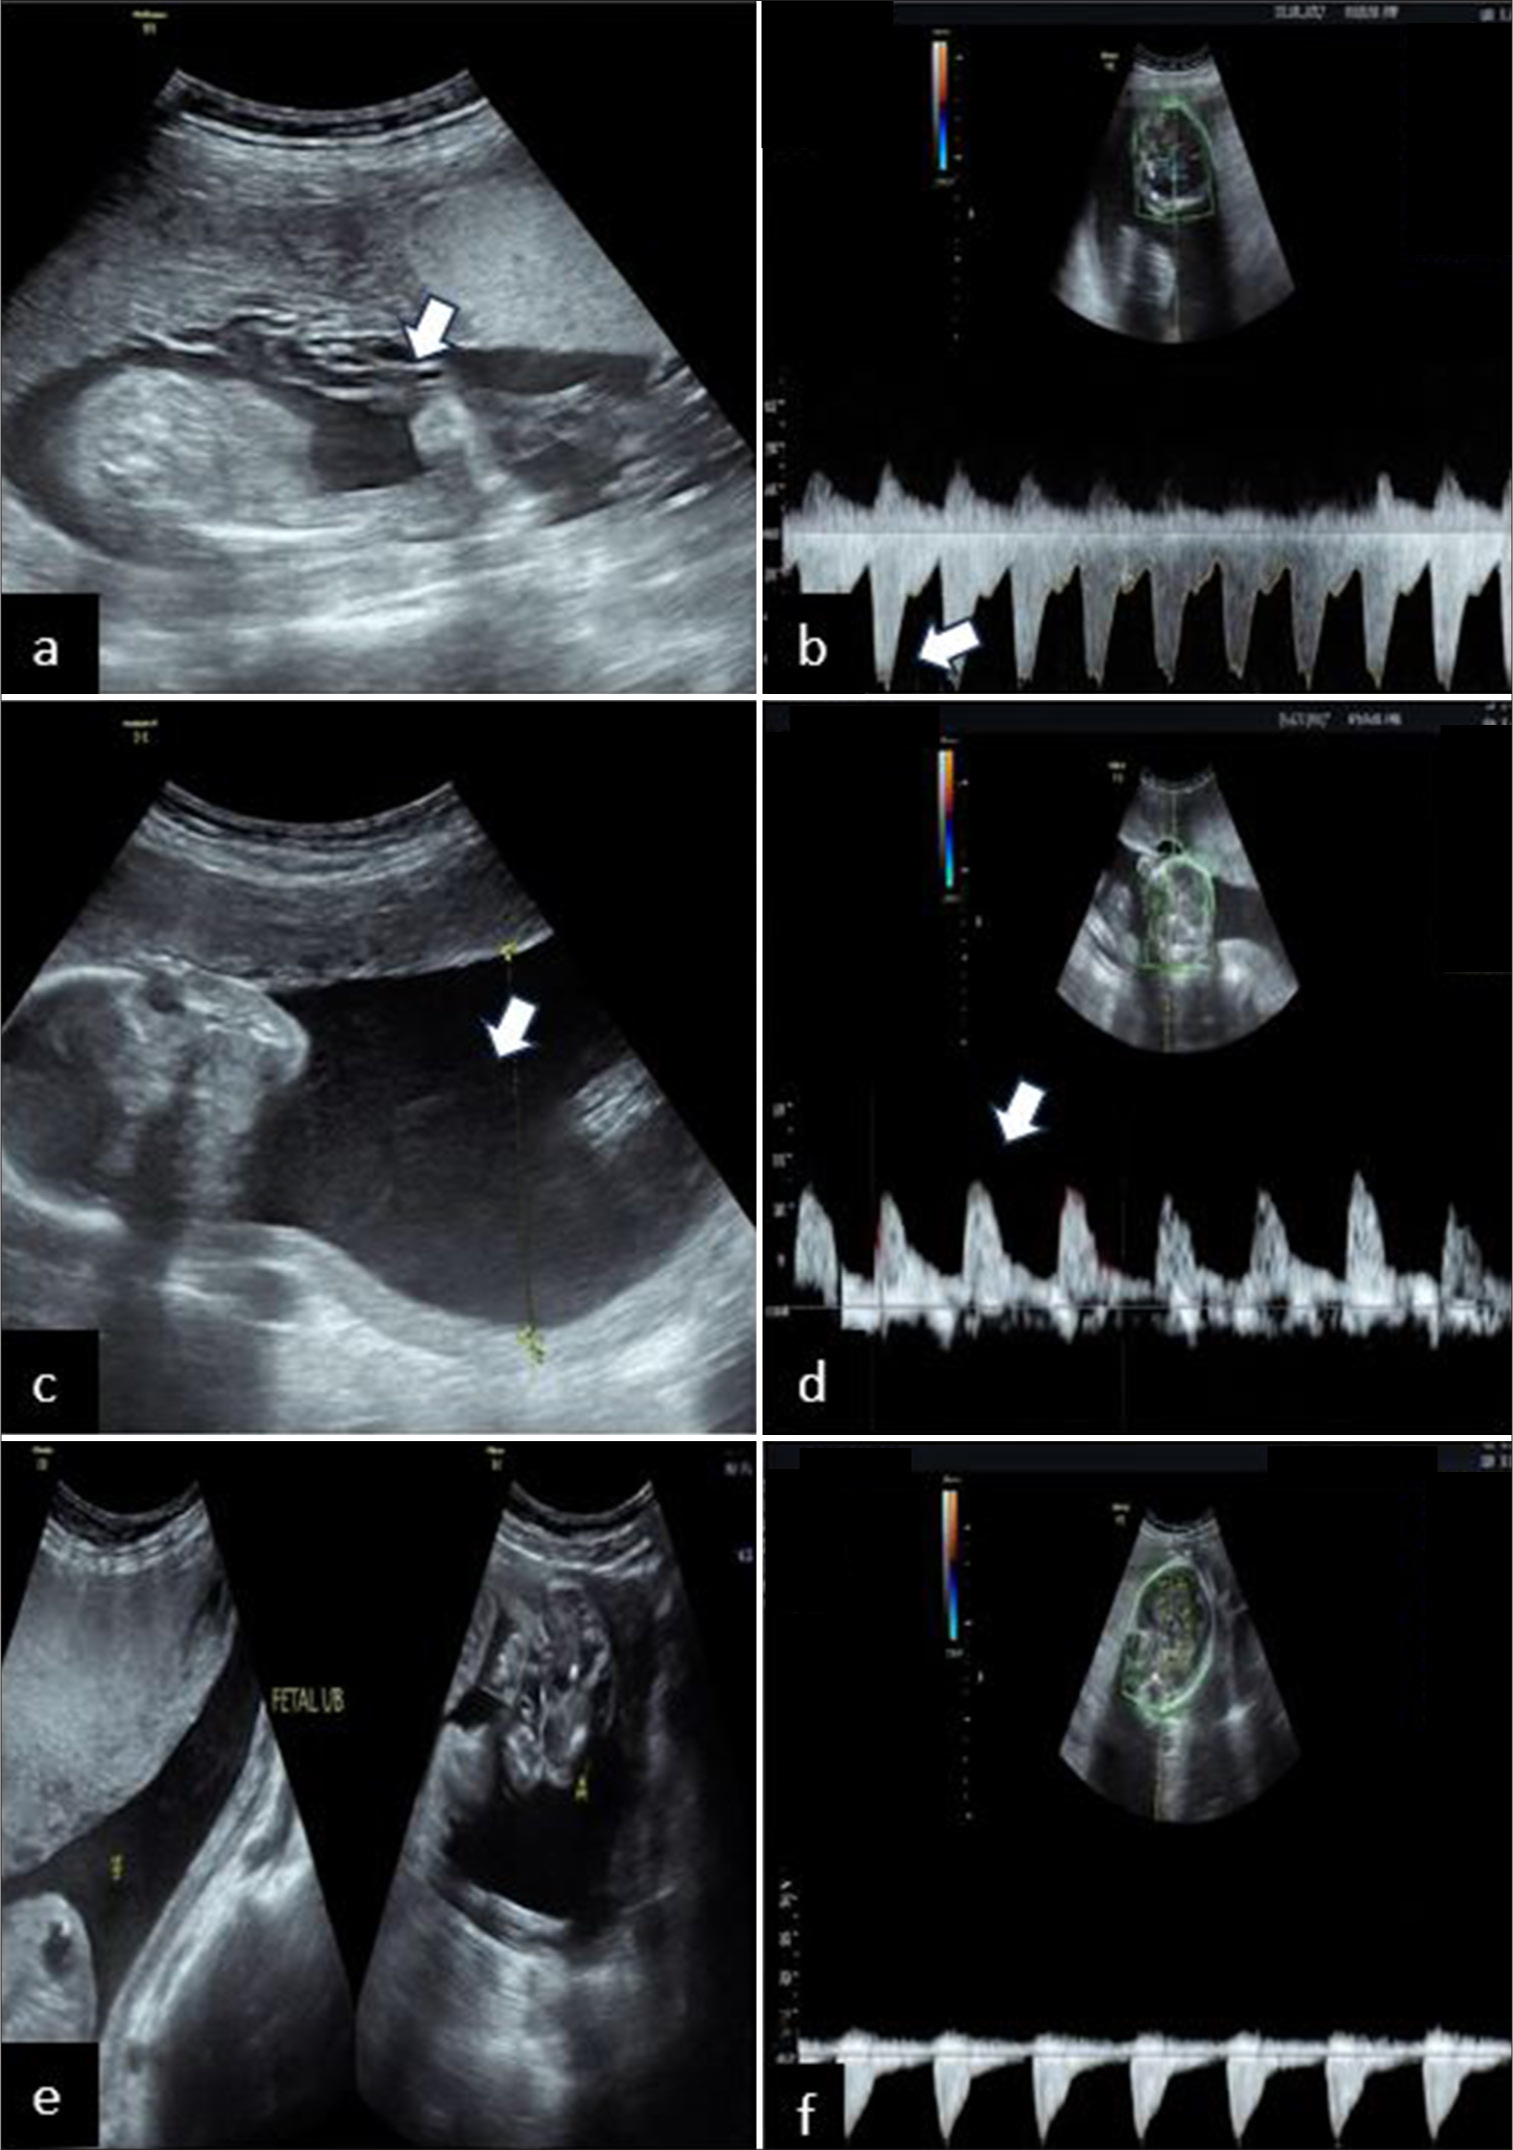

Yogesh Shardul, Anushka Mittal, Samrin Haq, Priyanka Garg